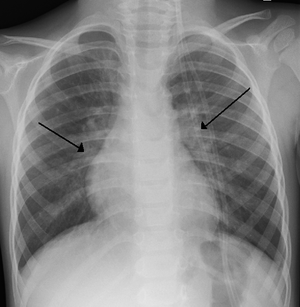

| An X-ray of a child with RSV showing the typical bilateral perihilar fullness of bronchiolitis. | |

The diagnosis is typically made by clinical examination. Chest X-ray is sometimes useful to exclude bacterial pneumonia, but not indicated in routine cases.[14]